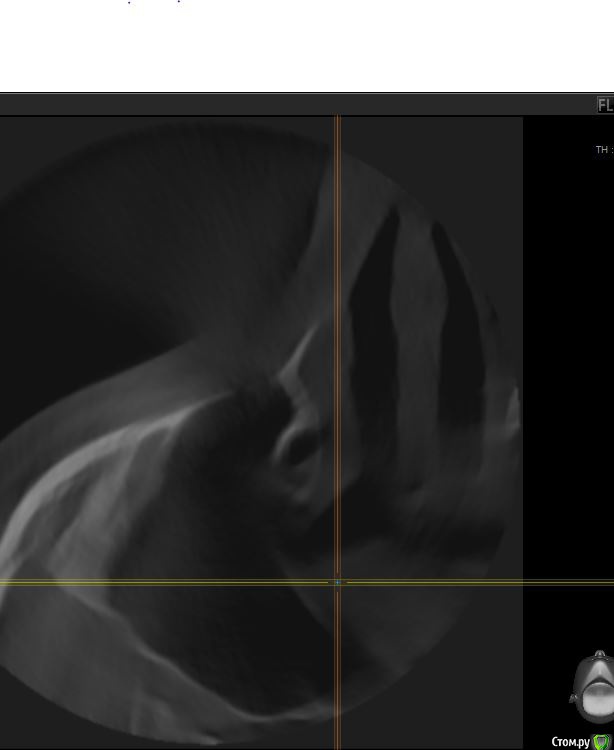

red_butler Опубликовано 12 июля, 2016 Поделиться Опубликовано 12 июля, 2016 Соустье покажите Ссылка на комментарий

jm3300 Опубликовано 13 июля, 2016 Автор Поделиться Опубликовано 13 июля, 2016 Соустье покажитетам кт заканчивается, не особо видно Ссылка на комментарий

jm3300 Опубликовано 14 июля, 2016 Автор Поделиться Опубликовано 14 июля, 2016 выкладываю кт Ссылка на комментарий